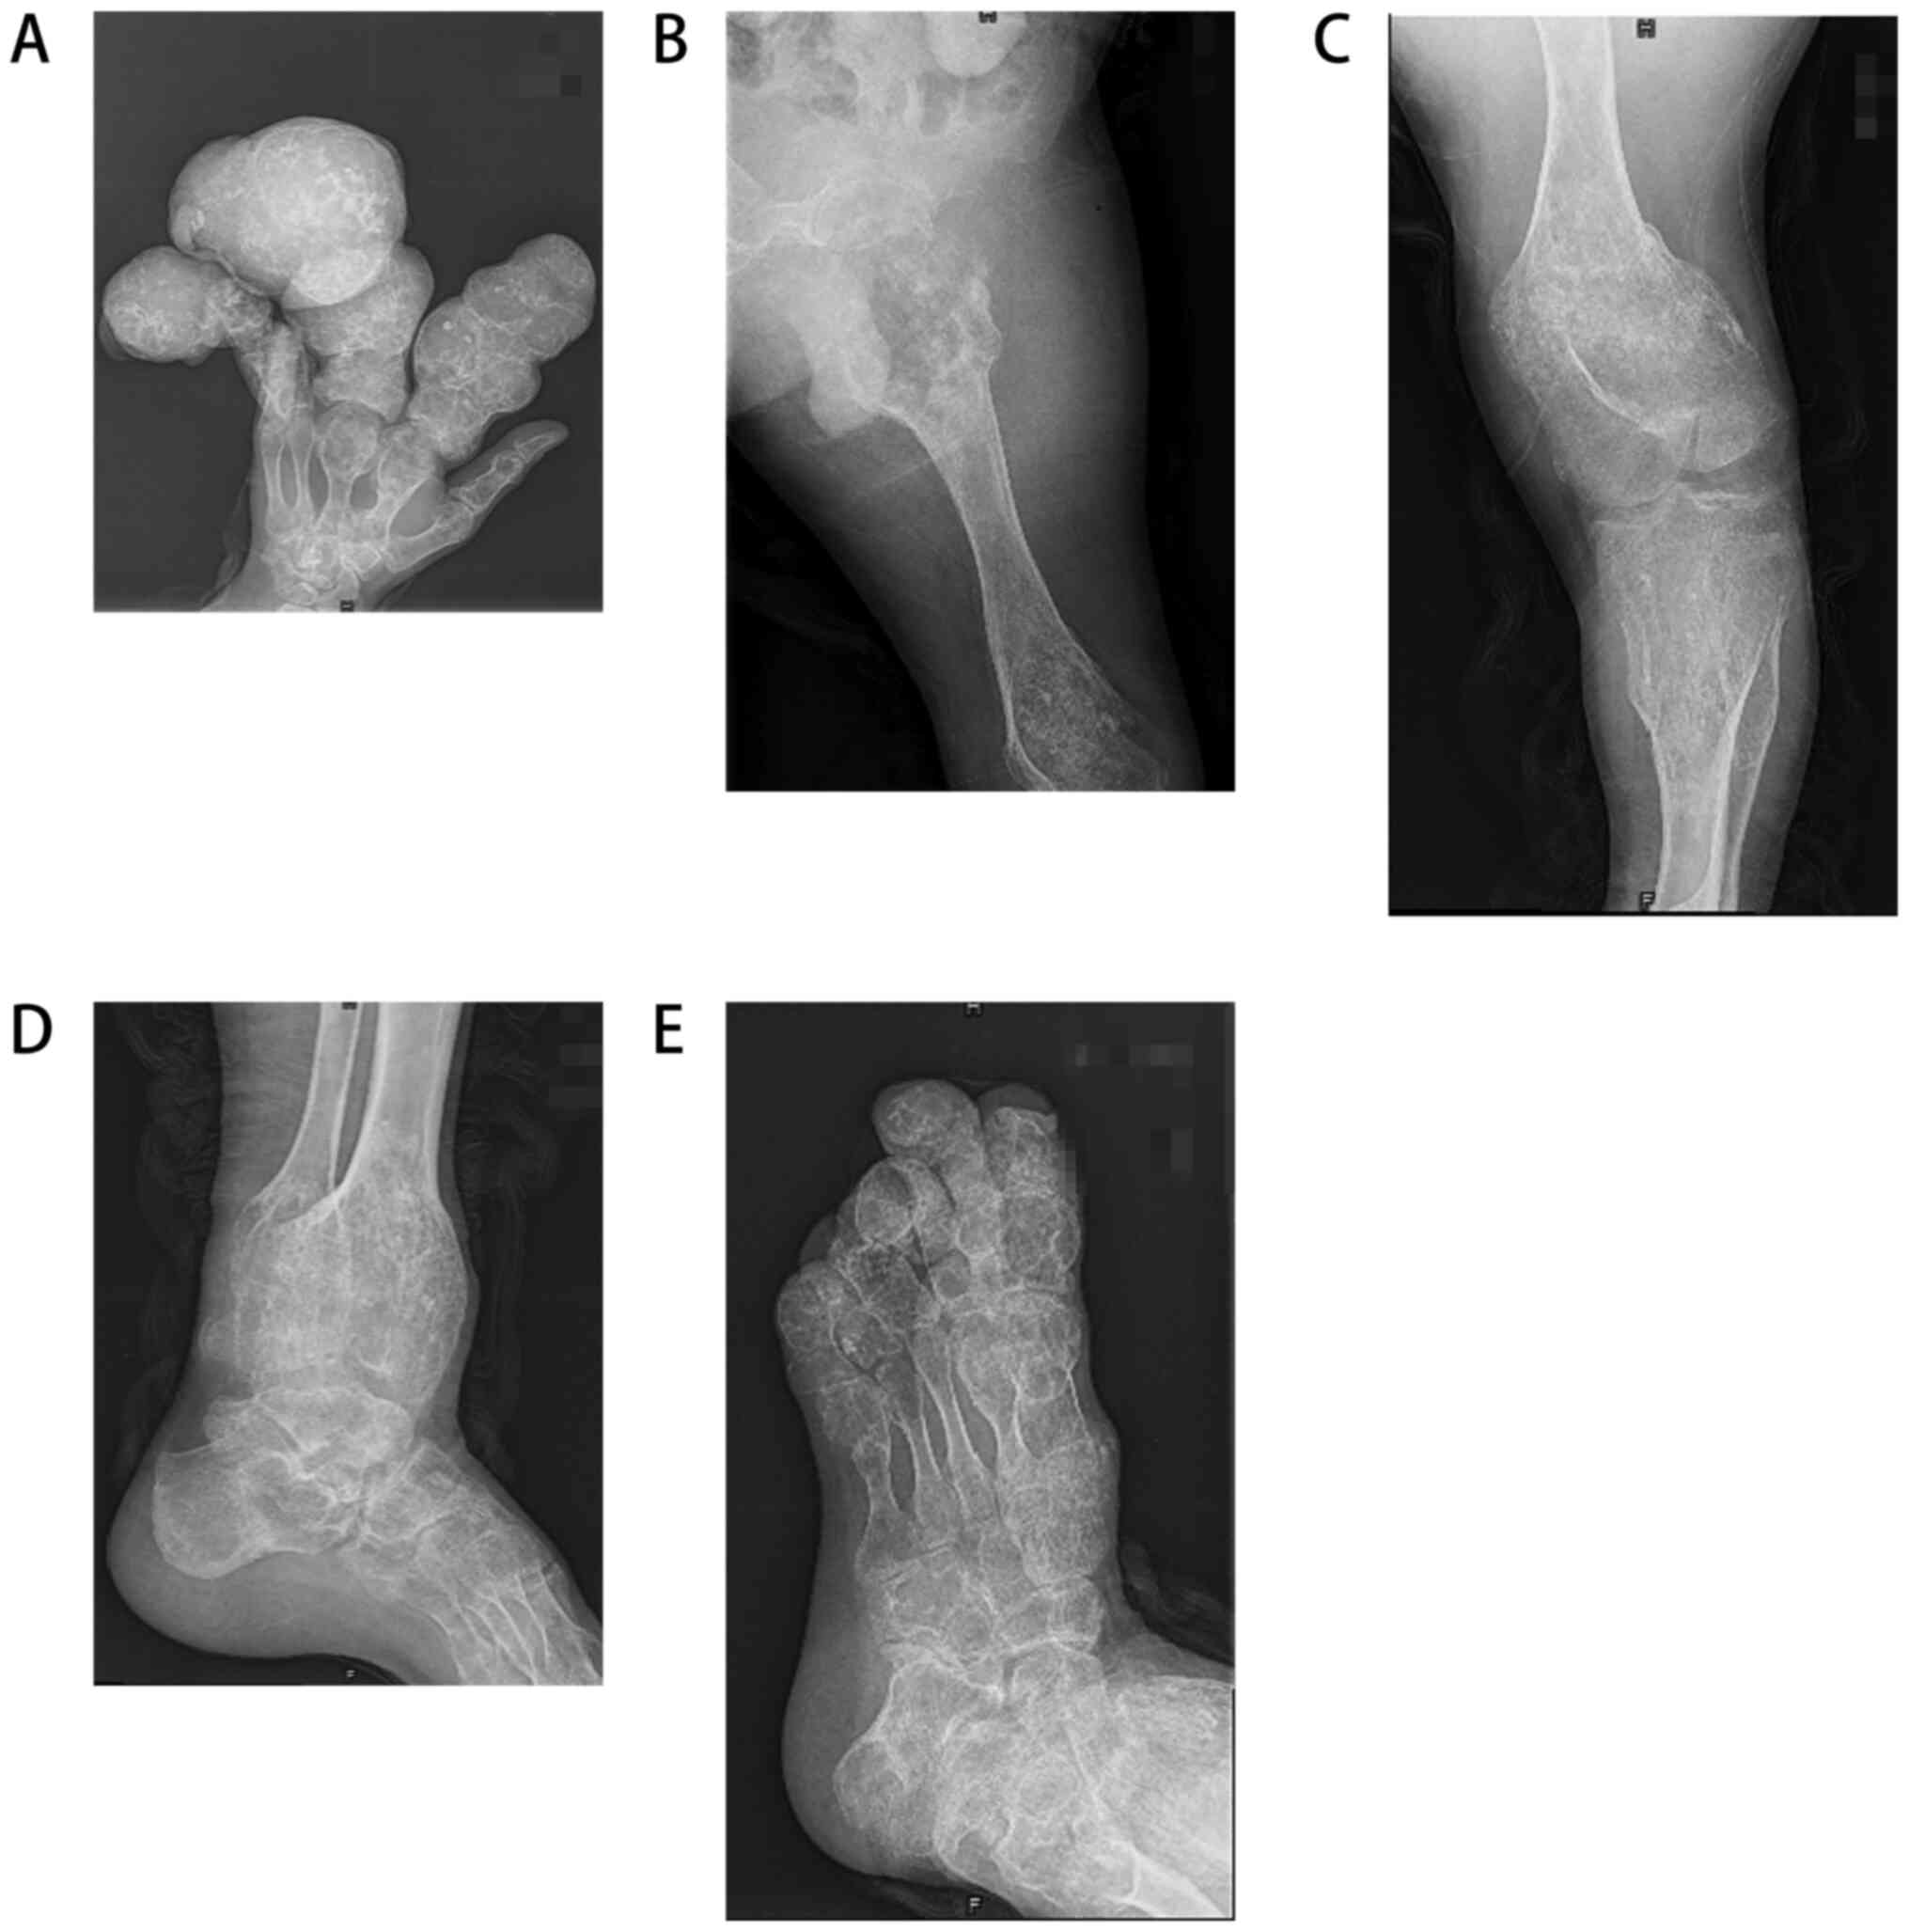

A 37-year-old man had initially developed an obvious mass on his left index, middle and index fingers at the age of 6 years; however, no special treatment was administered. After 30 years, the masses on the patient's hands had grown in size, acquiring a dendritic shape, and were accompanied by pain, leading to limited function and movement. Moreover, the left hand (Fig. 1A), left hip, left knee, left ankle and left foot (Fig. 1B) were swollen and this condition progressively became aggravated. The mass was hard and exhibited nodular changes. At a later stage, the mass in the left hip became rapidly enlarged and the patient was in obvious pain. He also visited relevant hospitals without receiving any special treatment. The patient came to the Second Affiliated Hospital of Shanxi Medical University for treatment in 2018 due to severe pain in the left hip joint. Since the onset of the disease, the patient did not have any symptoms of a frequent fever, fatigue, emaciation, dizziness, headaches, blurred vision or any other discomfort, In addition, the patient had no family history of any hereditary diseases, no history of exposure to any specific chemicals and radiation, and was a single farmer in occupation and did not use tobacco and consume alcohol. A physical examination upon admission revealed the following: The left lower extremity of the patient was significantly shorter than the right lower extremity, by ~10 cm. Dendritic-shaped masses were observed in the left hand, swelling and deformity were observed on the left hip, left knee and left foot, and the range of motion of the left hip and left knee was markedly restricted compared with that of the normal right hip and knee. An X-ray examination revealed multiple osteopathies of the left hand, left hip, left knee, left ankle and left foot (Fig. 2). A magnetic resonance imaging (MRI) examination of the hip revealed abnormal signals of bone and soft tissue in the proximal left femur (Fig. 3), and malignant lesions were considered. The clinical diagnosis of Ollier disease was thus made. The results of the patient's laboratory tests are presented in Table I. However, due to the clear diagnosis, the patient did not undergo radionuclide bone imaging and a computed tomography (CT) scan.

Figure 2

Localized bone destruction and bone expansive growth in the (A) left hand, (B) left hip, (C) left knee, (D) left ankle and (E) left foot.

Imaging diagnosis

Radionuclide bone imaging is the most effective tool for the diagnosis of multiple lesions and malignant transformation (20). It can guide the clinical and prognostic analysis of Ollier disease. An X-ray is one of the most basic tools for the diagnosis of skeletal diseases. In Ollier disease, the lesions mostly appear in the shaft and metaphysis of short or long bone, and the lesions are mostly oval in shape. In short bone, the lesions can appear as scallop-like impressions due to the limited space, the cortical bone becomes thinner, and thus pathological fractures are common. In the long shaft, due to its large growth space, there is no characteristic scallop-like impression, and the bone cortex does not become thinner (21). It is more important to evaluate the lesion size and soft tissue invasion by a CT scan (16). The lesion is characterized by a round and lobulated density shadow, and the density is equal to or slightly lower than the muscle density shadow (22). A CT scan can also reveal different calcification patterns. It has been indicated that further attention should be paid to calcification patterns when predicting the development of chondrosarcoma (18). In the present study, the MRI revealed a round, quasi-round and striped density inhomogeneous signal in the medullary cavity, particularly soft tissue involvement. For example, in the present study, the MRI revealed the significant destruction of the left femoral cortex and extensive soft tissue involvement, combined with the rapid aggravation of short-term pain in the patient, considering the greater possibility of malignant chondrosarcoma; a biopsy also needs to be performed to determine the nature of the lesion before guiding clinical treatment.

On the whole, an X-ray can diagnose correctly typical cases. A CT scan can reveal calcification foci, which is of great significance in determining whether there a malignant alteration exists. An MRI examination can visualize the cartilage components in the lesions to further clarify the lesions and improve the accuracy of diagnosis.